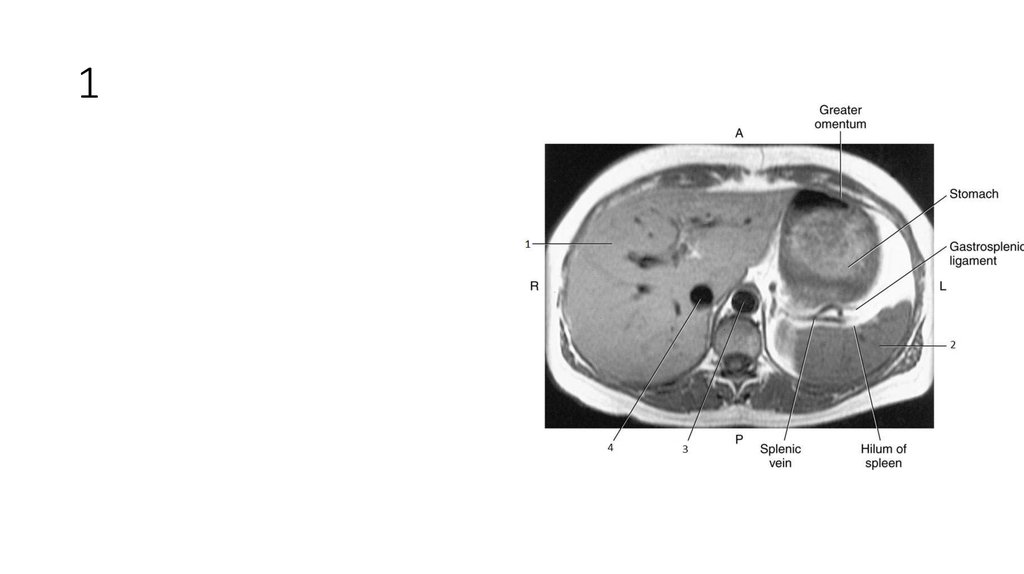

1

2

3

4

5

6